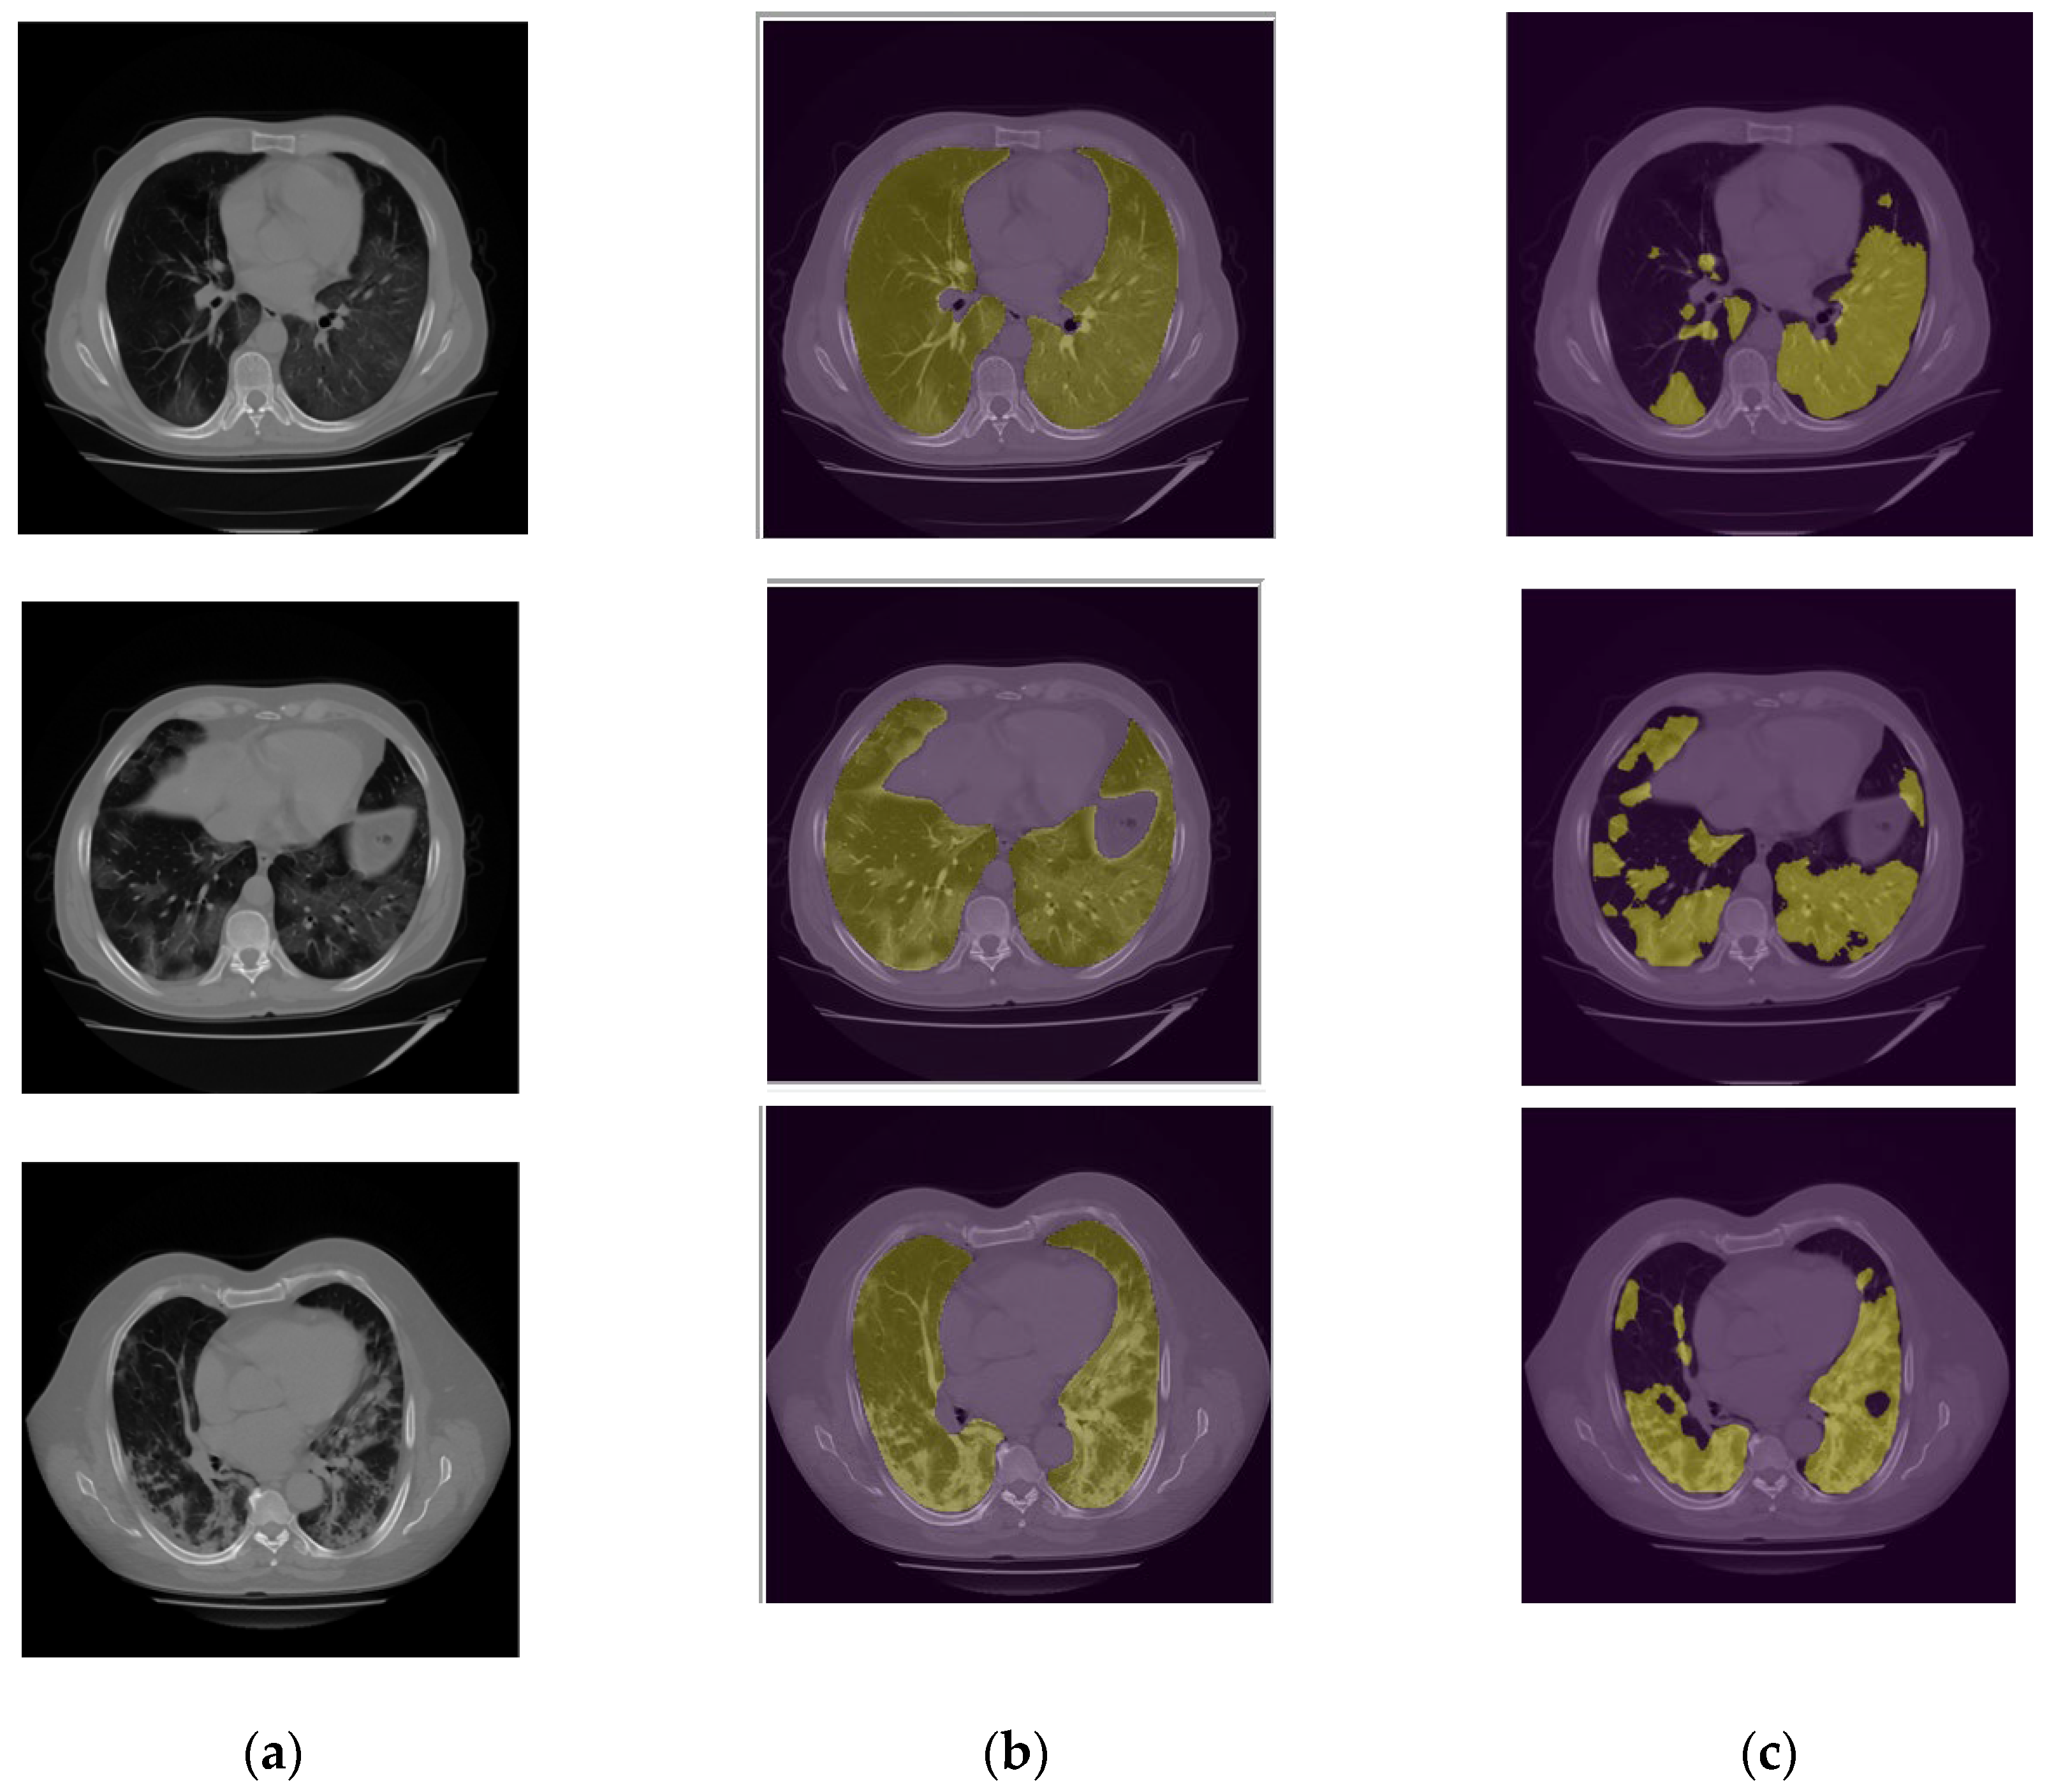

Figure 7 demonstrates several examples of the lung and infection segmentation results. The left column illustrates the raw CT images while the second and third columns illustrate the masks of the segmented lung and disease infection areas, respectively. In addition, Figure 8, shows the patch segmentation results of GGO and consolidation areas (or blobs).

Figure 7. (a) Raw CT image (b) Lung mask and (c) Infection Segmentation.